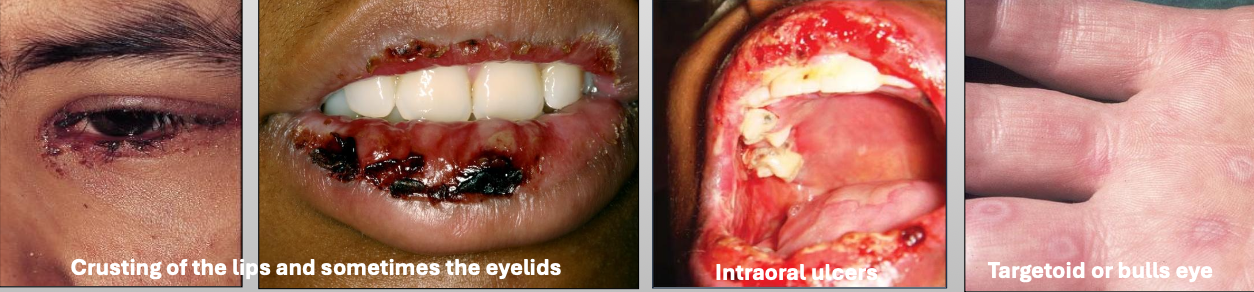

What is Erythema Multiforme (EM)

A blistering ulcerative mucocutaneous condition of uncertain pathogenesis. You see a spectrum of hypersensitivity reaction. The sisease lasts 2-6 weeks (self limiting); 20% have recurrent episodes

What is the cause of Erythema Multiforme (EM)?

Herpes virus (HSV)

Mycoplasma pneumoniae

Medications

What are the clinical features of Erythema Multiforme (EM)

You get prodromal signs a week before

Crusting of the lips and sometimes the eyelids

Intraoral ulcers

Targetoid or bulls eye

What demographic does Erythema Multiforme (EM) affect?

Young M>F

What is the treatment for Erythema Multiforme (EM)?

Steroids

IV rehydration

Topical anesthetic

Discontinue drug

What are characteristics of minor Erythema Multiforme (EM)?

Mild

Young, Male > female

Starts on skin of extremities, oral lesions appear

Crusting on lips

Usually due to herpes (HSV)

What are characteristics of major Erythema Multiforme (EM)?

Wide spread skin lesions + 2 or more mucosal sites

(Oral + ocular or genital)

Ocular scarring may occur in severe cases (Symblepharon)

Usually due to herpes (HSV)